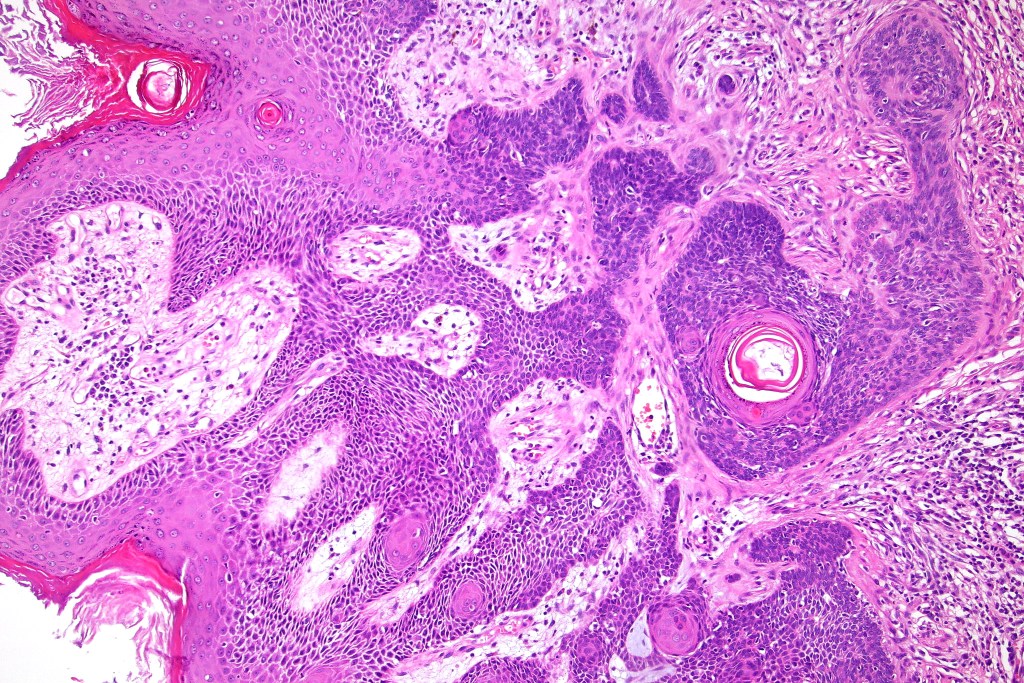

•Sharply circumscribed, unencapsulated nodule in deep dermis +/- subcutaneous fat or deeper (trichoepithelioma is much more superficial)

•Variably sized but generally large, basophilic tumor nodules composed of small uniform basaloid cells with minimal cytoplasm

•Peripheral palisading but no retraction artifact or stromal mucin deposition

•Variable keratocysts

•A rich fibromyxoid mesenchymal stroma with variable papillary mesenchymal bodies (sometimes these are absent)